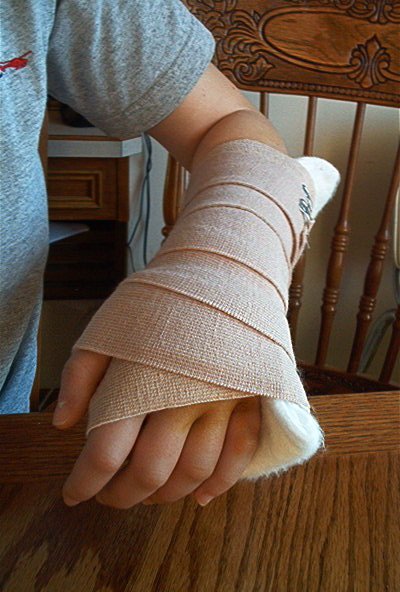

Cheryl's Zipper Cast

Swelling More swelling A few weeks later

After the Shortening Finger Swelling

After Shortening 2 Weeks Post-Op Stitches Out